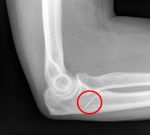

Несмотря на свой возраст, 41-летний англичанин продолжал играть в большой теннис. Когда у него начались боли в локте, врачи решили, что это спортивная травма. Но боли лишь усиливались. Между тем, первый же рентген показал, что в локте у него игла.